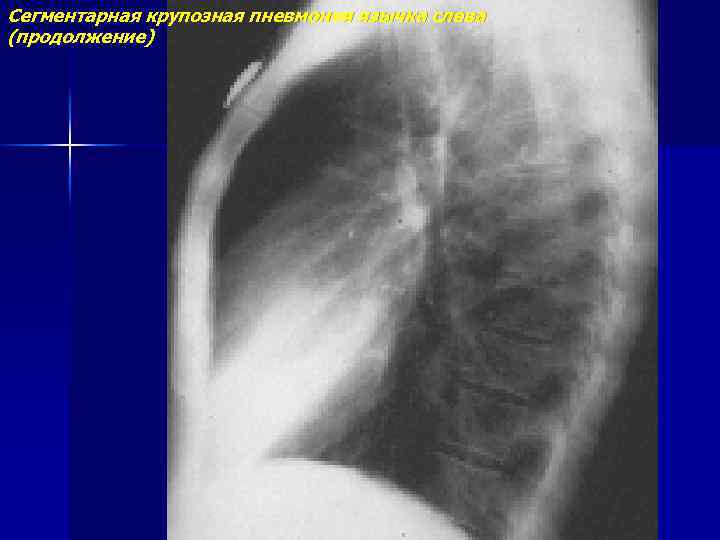

Сегментарная крупозная пневмония язычка слева (продолжение)